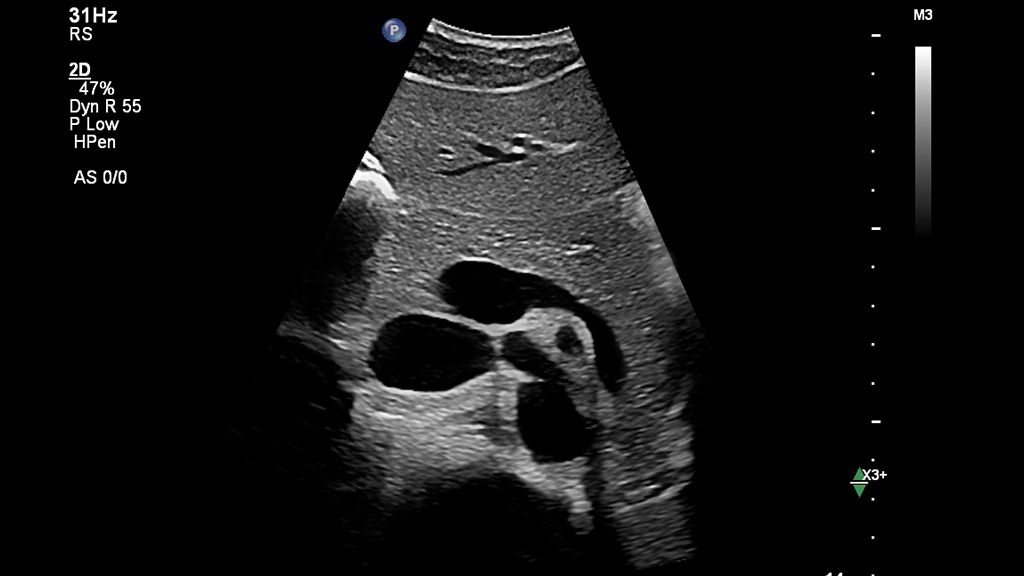

Auto Measure Abdomen

Standard workflow vs. Auto Measure Abdomen workflow

See how much time you can save with Auto Measure Abdomen in this side-by-side workflow comparison video.

The widespread use of this technology in a general population could be helpful in screening for advanced chronic liver disease, especially considering that a complete study can be done in under three minutes using a non-invasive method for chronic liver disease.